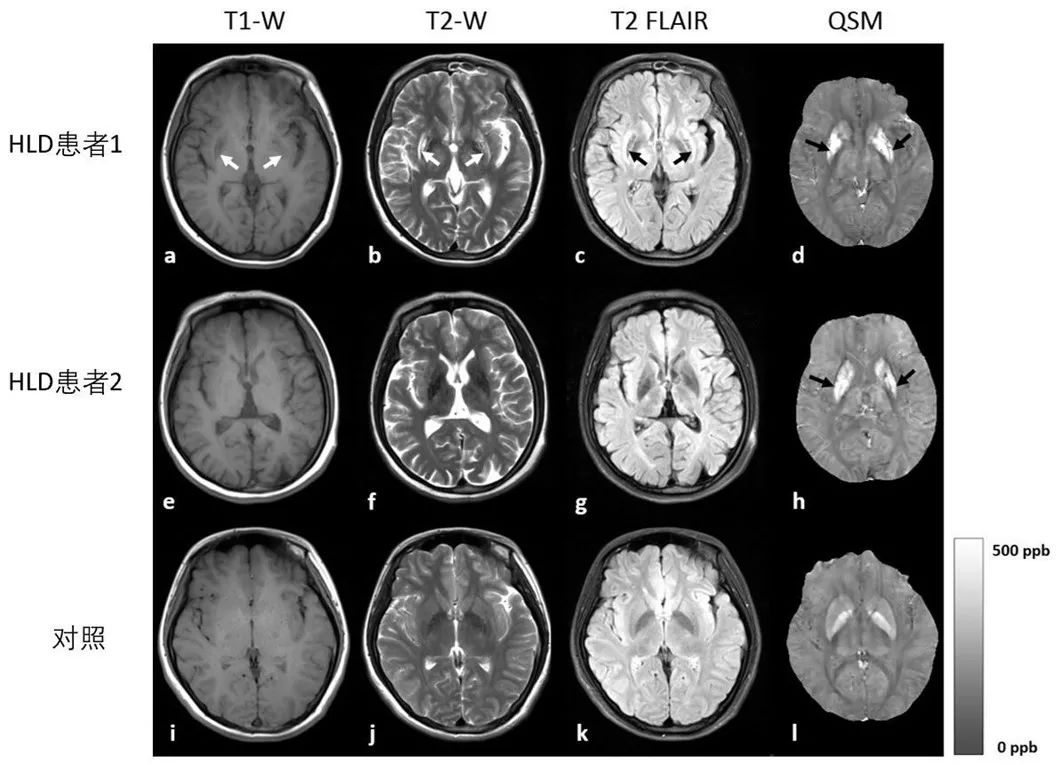

肝豆状核变性,是一种铜代谢障碍相关的常染色体隐性遗传疾病。其发病机制为 ATP7B 基因突变,导致铜转运 P 型 ATP 酶结构和功能异常,铜在肝脏、脑、角膜等部位异常沉积,造成相应器官的损伤。作为铁氧化酶的铜蓝蛋白合成减少,同时也导致患者体内铁代谢障碍。根据近期大规模全基因组测序研究结果,ATP7B 杂合突变携带率约为 1/40,该病预计发病率为 1/7000,远高于其他神经系统遗传疾病。如何能利用影像学方法早期精准诊断 HLD、对体内铜铁分布进行动态观察、根据患者铜铁蓄积情况制定个体化治疗方案,是目前亟待解决的问题。本研究通过对肝豆状核变性患者脑深部灰质核团的磁化率和 R2*图的定量和定性评估来区分肝豆状核变性患者和健康对照组,并且评估上述两者对于在诊断肝豆状核变性时的敏感性。研究发现定量磁化率和 R2*可以有效区分不同的病变类型。磁化率和 R2*值在肝豆状核变性患者多种深部核团中显著高于正常对照组。磁化率值在黑质区域有最大的曲线下面积(0.888)。在尾状核 (r = 0.757, P = 0.011)、壳核 (r = 0.679, P = 0.031)、红核 (r = 0.638, P = 0.047) 中,统一肝豆状核变性评估量表值和磁化率值呈正相关,而在尾状核 (r = 0.754, P = 0.012) 中,其与 R2*值也呈正相关。

本研究是利用定量磁化率成像和 R2*图对肝豆状核变性患者脑深部核团金属沉积开展相关分析,定性分析发现,HLD 患者豆状核有三种类型的病变。QSM 在区分 HLD 患者不同类型的病变方面表现良好,为 HLD 中不同类型的病变的诊断提供了辅助信息。在大多数深部核团中,QSM 在区分 HLD 患者与健康对照组方面比 R2*更准确。在 HLD 患者与健康对照组的对比中,中脑核团(黑质和红核)在 QSM 和 R2*中表现出的差异较基底节核团(尾状核、壳核和苍白球)和小脑核团(齿状核)更加明显。患者临床症状评分分数(统一肝豆状核变性评分量表,UWDRS)与 HLD 受试者尾状核的磁化率值之间存在显著的正相关关系。QSM 或 R2*值与其他临床指数没有相关性,特别是尿铜和血清铜蓝蛋白。进而,我们认为基于 3.0 T MRI 的定量磁化率成像是评估肝豆状核变性患者脑深部灰质核团中金属沉积情况的有效手段。